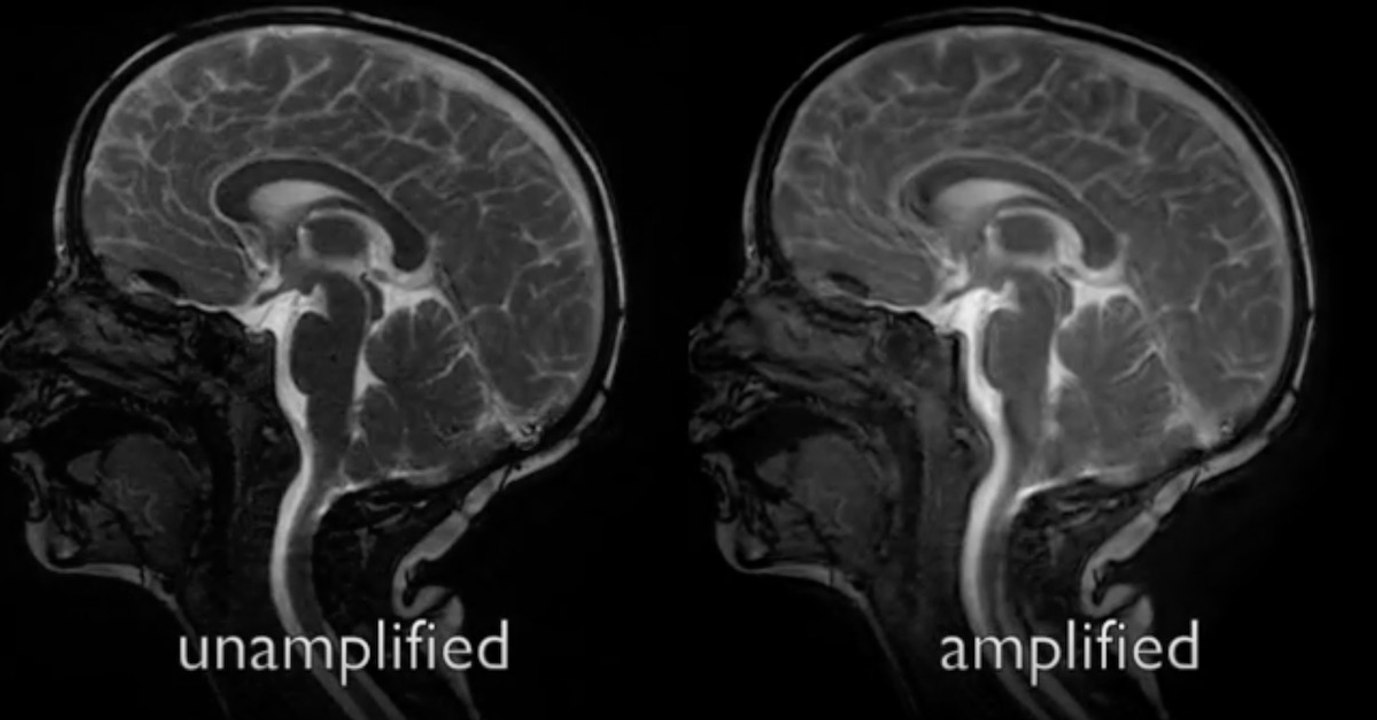

Des chercheurs révèlent les étonnants mouvements qui agitent le cerveau lorsque le coeur pompe le sang

Gentside Savoir